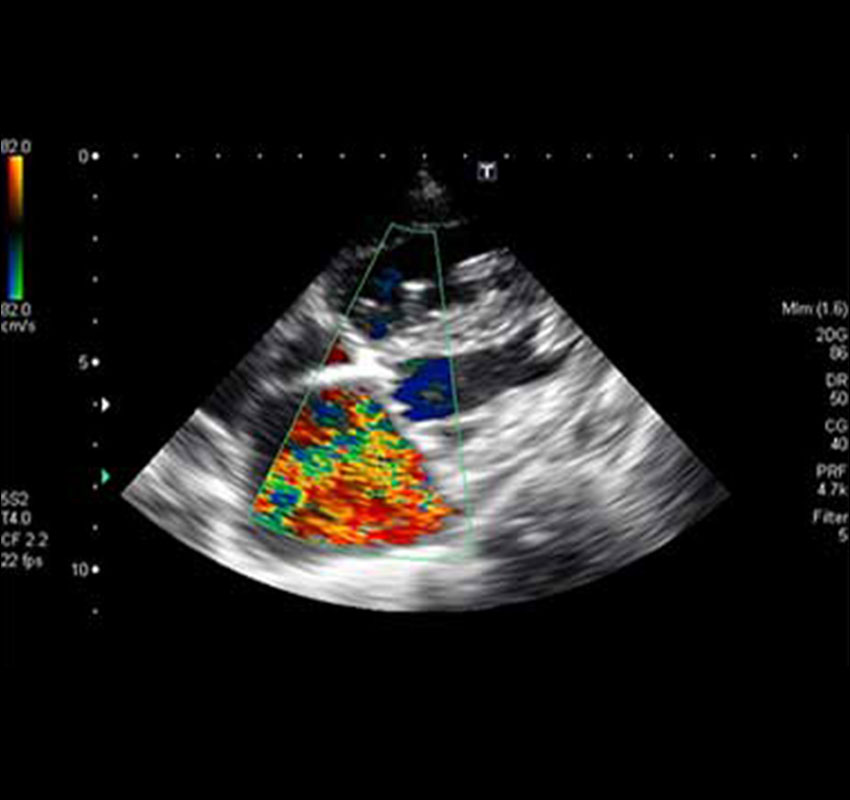

- Ultrasound- Cardiac, Abdominal, Pregnancy evaluation